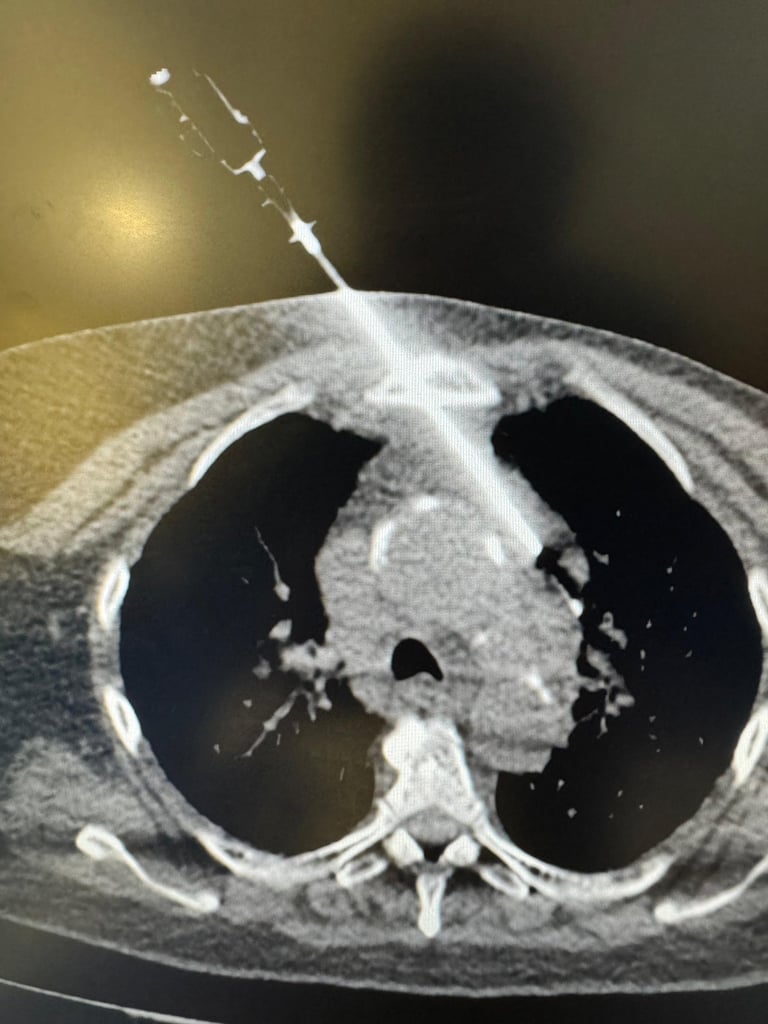

Ablações Percutâneas

Ablação por radiofrequência (RFA)

Ablação por micro-ondas

Crioablação

Ablação química (álcool, ácido acético)

Ablação de tumores hepáticos, renais, pulmonares, ósseos e de partes moles

Biópsias pulmonares